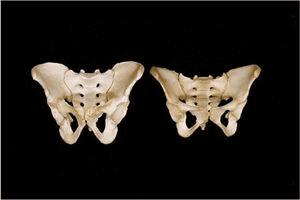

14.女性的盆骨(右侧)比男性的盆骨(左侧)更宽、颜色更淡。女性盆骨底部的耻骨角度更宽,便于生小孩。